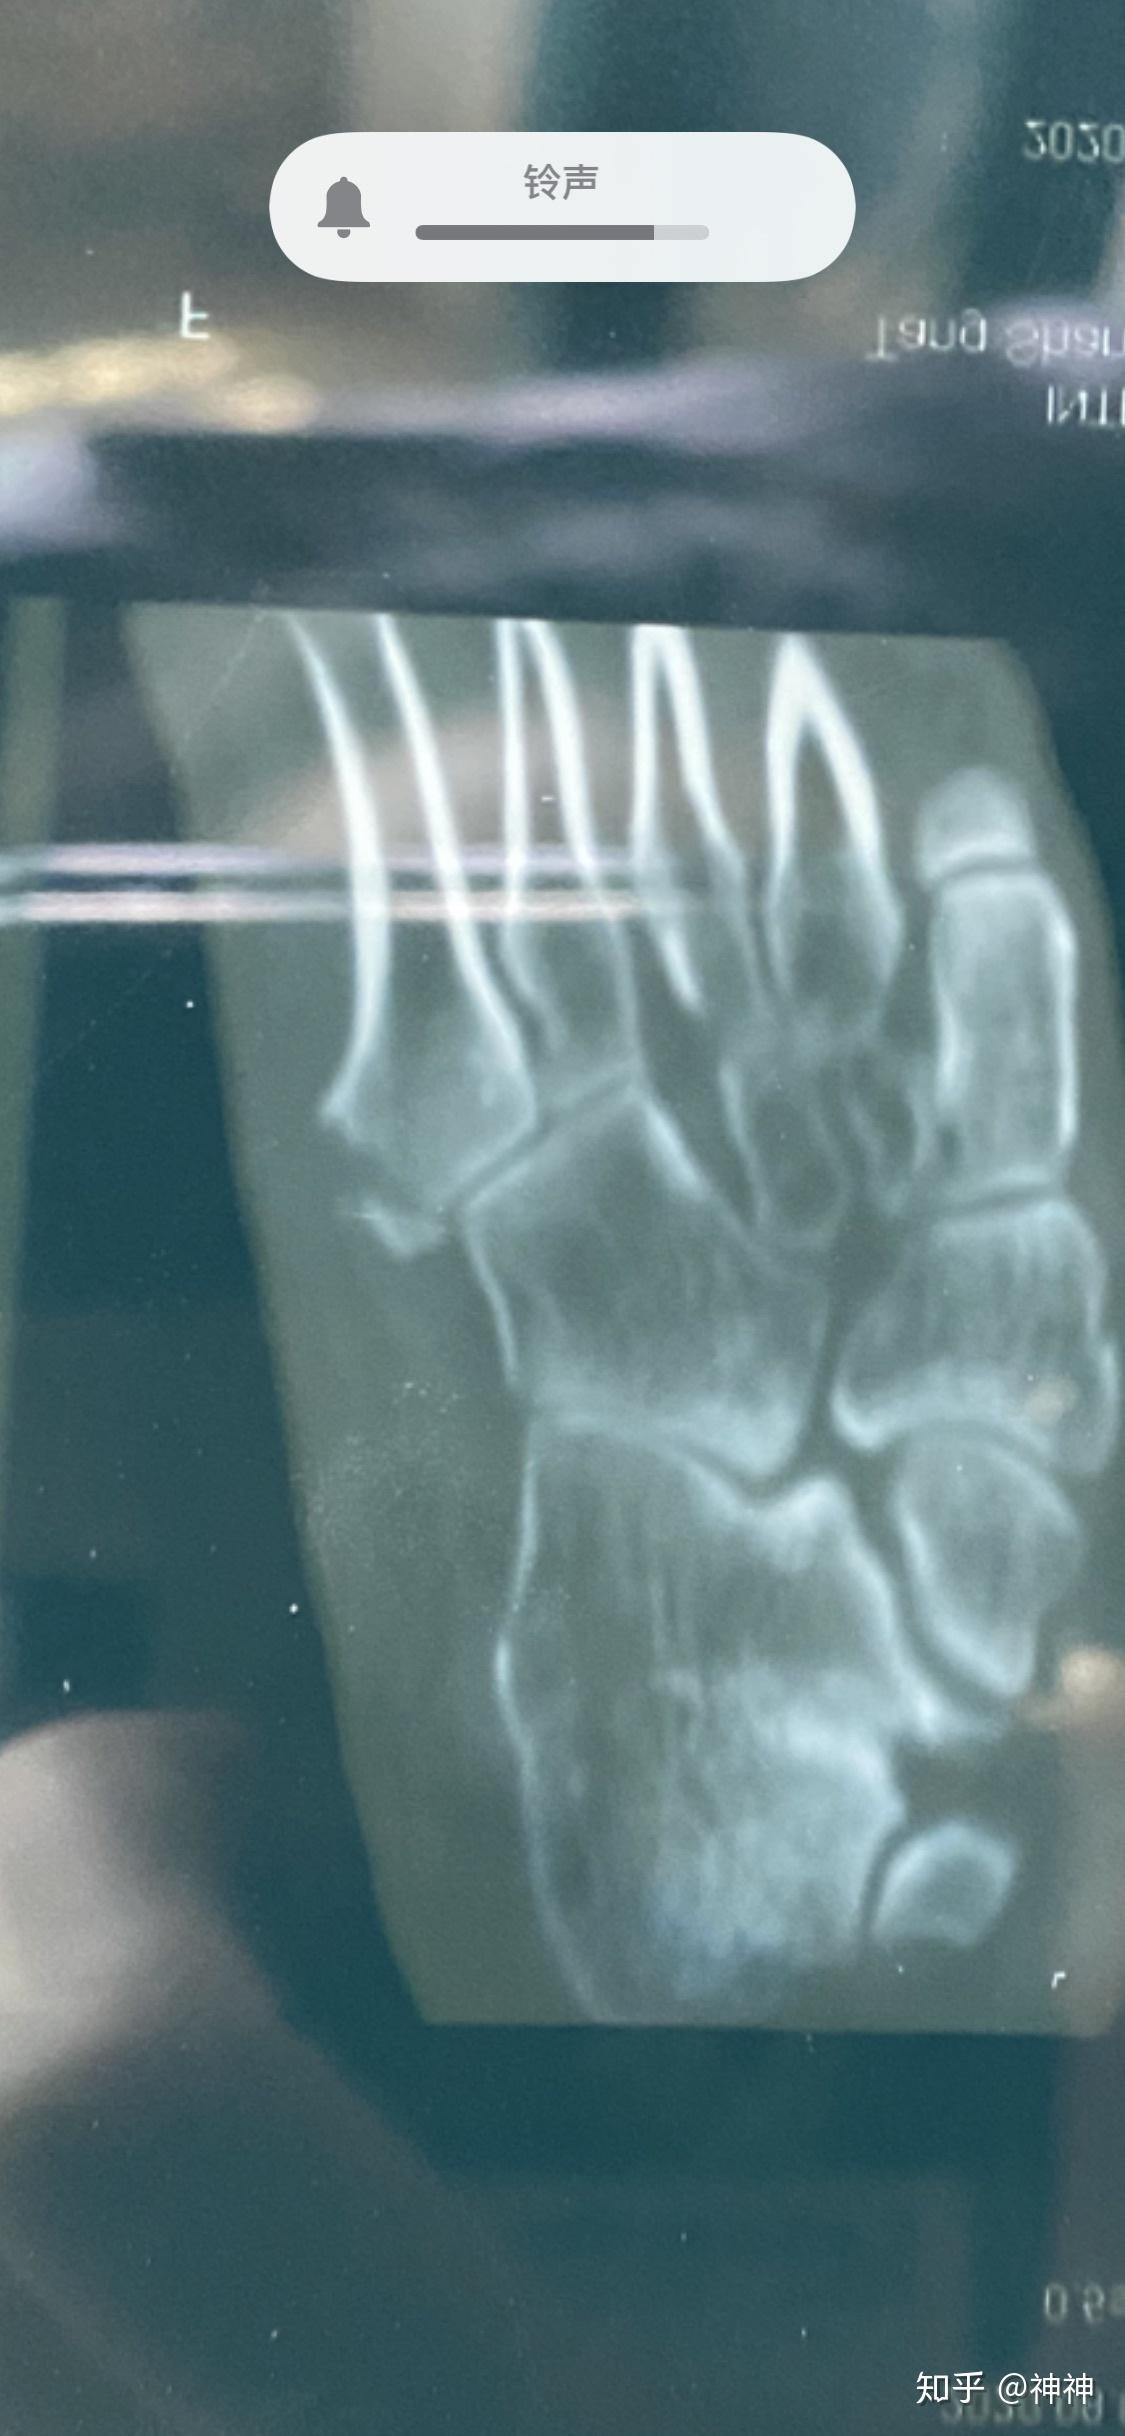

第五跖骨基底骨折缝隙有点大需要手术吗